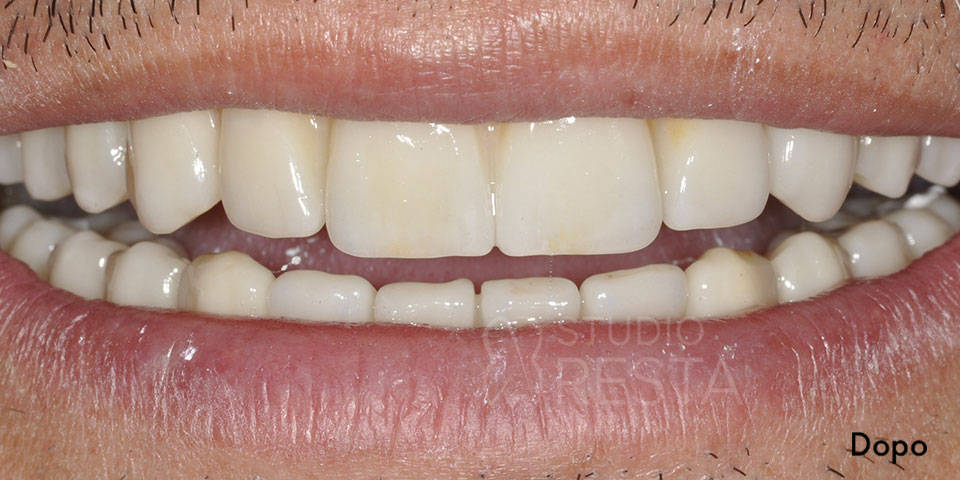

All on 4 senza gengiva finta: estetica naturale

Una domanda frequente riguarda l’eventuale presenza di gengiva artificiale rosa sulla protesi All on Four. In alcuni casi, soprattutto quando l’osso e i tessuti si sono molto riassorbiti, le protesi su impianti completi presentano una flangia rosa che simula la gengiva mancante. Tuttavia, realizziamo spesso protesi All on 4 senza gengiva finta, ottenendo un’estetica straordinariamente naturale. Questa opzione protesica avanzata evita l’antiestetica “fascia rosa” visibile quando si ride, risultando praticamente identica a una dentatura naturale che emerge dalle proprie gengive.

Ovviamente la fattibilità di un’All on 4 senza gengiva finta dipende dal caso clinico: serve che il sorriso del paziente non mostri troppo la zona gengivale e che sia possibile realizzare denti di dimensioni appropriate per compensare la perdita di tessuto. Quando le condizioni lo permettono, però, preferiamo garantire protesi totalmente bianche (solo denti) per un risultato estetico ottimale. Il vantaggio è duplice: un aspetto più realistico e la sensazione per il paziente di “avere veramente i propri denti” in bocca, senza alcuna protesi visibile. Durante la visita pre-operatoria valuteremo anche questo aspetto estetico, concordando con il paziente la soluzione migliore in base alle sue aspettative di sorriso.

All on Four Senza Gengiva Finta

L’implantologia All on Four senza gengiva finta è un’opzione protesica che non prevede l’utilizzo sulle protesi dentali di gengiva artificiale. Questo approccio consente un’estetica migliore e soprattutto un aspetto più naturale delle protesi in modo da renderle perfettamente mimetizzabili.